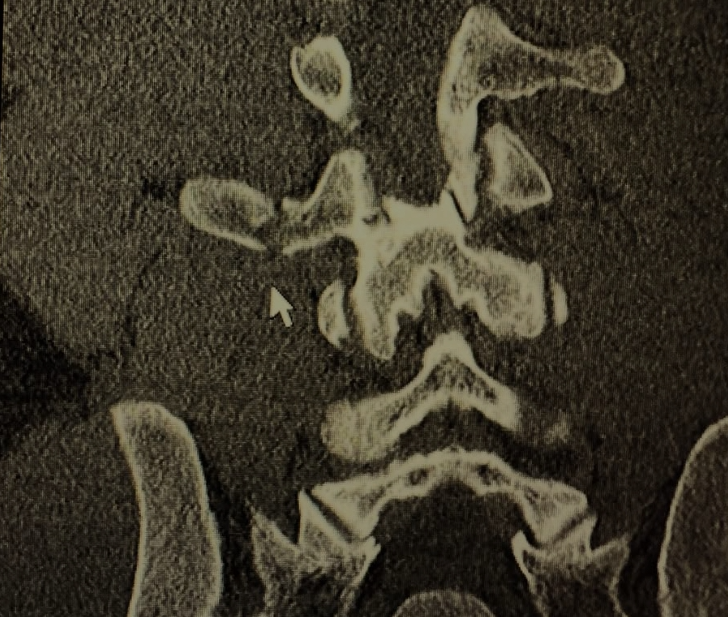

Tuesday night Sergio had a bicycle accident. He took a corner going 30 mph+, pedaled down and clipped the pavement launching him over his handlebars and flat onto his back. He broke the transverse process of L2,3,4.